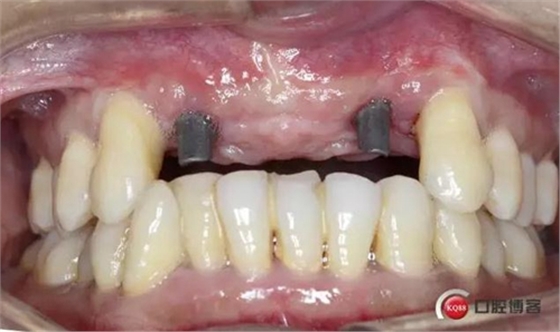

戴入修復(fù)基臺(tái)